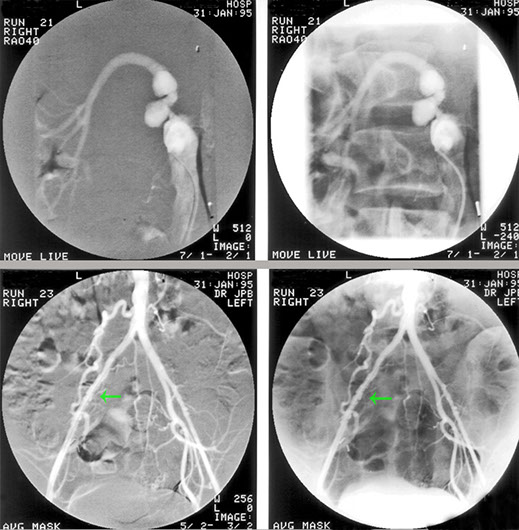

Fibromuscular dysplasia has a beaded appearance of narrowing and dilatation of the vessel wall and should be considered when a young patient presents with hypertension.

On the whole, fibromuscular dysplasia can be satisfactorily treated by balloon angioplasty. However, in this patient, it was not successful and surgical correction by a graft between abdominal aorta and renal artery was carried out.

However, the graft again stenosed as you can see. Fibromuscular dysplasia may affect many arteries and here the arrow is pointing to disease of the right common iliac artery in the same patient.